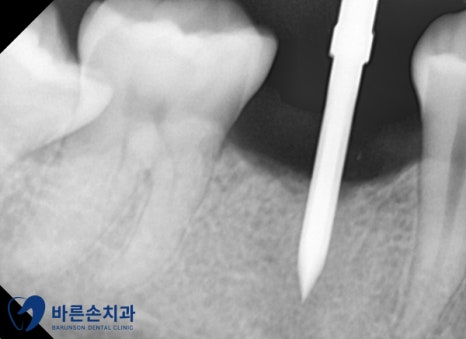

임플란트를 심을 위치를 확인하고 신경까지의 거리를 보기 위해

엑스레이를 찍어 확인합니다.